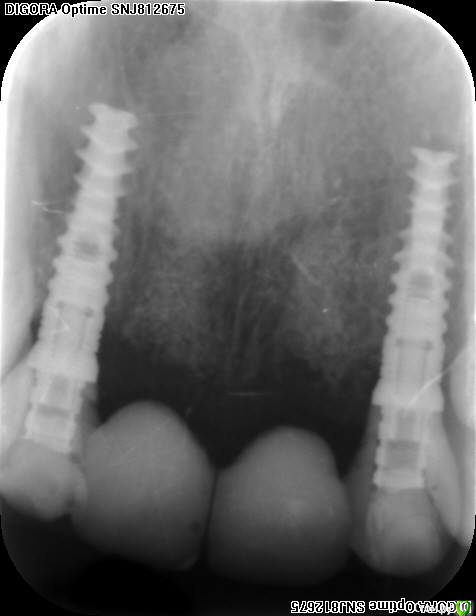

an_ver Опубликовано 16 сентября, 2016 Поделиться Опубликовано 16 сентября, 2016 Скинте или на ФБ в личку фото/снимки, или на электронную почту,Чем смогу - помогу. Вот что было до консультации с Анастасией(((..пациентка удаляла и ставила импланты в другой клинике.Обратилась ко мне через знакомых.Мной сделано до фото,шашлыки на 12,22,новые временные коронки через вакс ап, фото через 4 месяца после иплантации..и...дальше...примерно знал как делать..но сомневался. После длительных))) (потому что не сразу я понял) консультаций решил взять нож в руки..сегодня снял швы..прошла неделя. Спасибо Анастасия за консультацию и самое главное терпение, я не очень понятливый)) студент.Да, и если есть возможность,коллеги,как говорит Эдуард,делайте все сразу,особенно десну, потом легче будет 10 Ссылка на комментарий